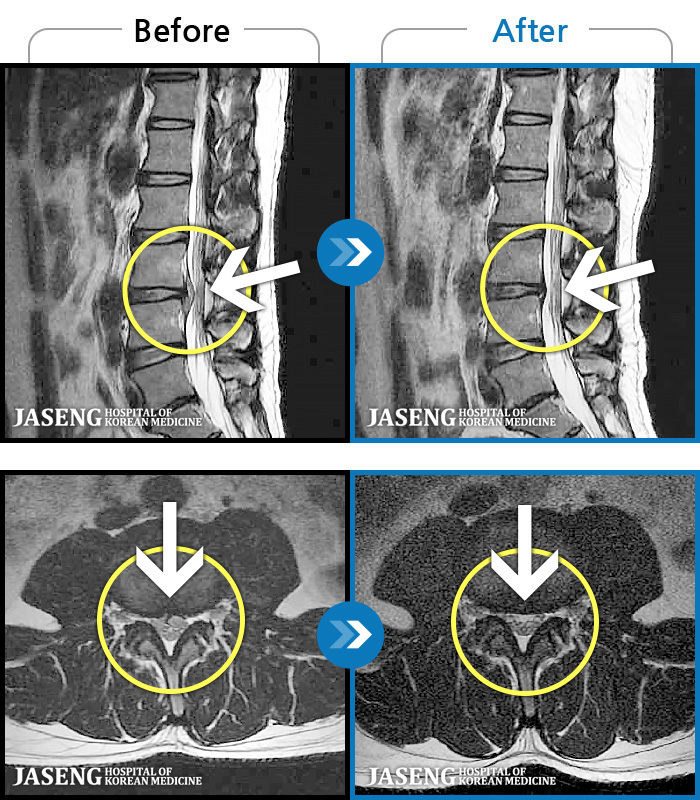

1,237 MRI ũ ʸ Ȯϼ.

1,237